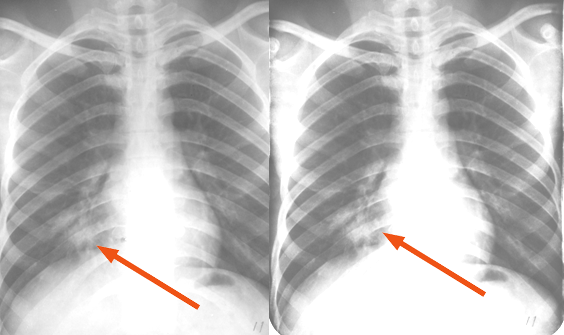

右肺中叶大叶性肺炎正侧位

图片

胸部正侧位片:右肺中叶见片状致密影,边缘模糊,局部呈剪影样改变(红圈所示)